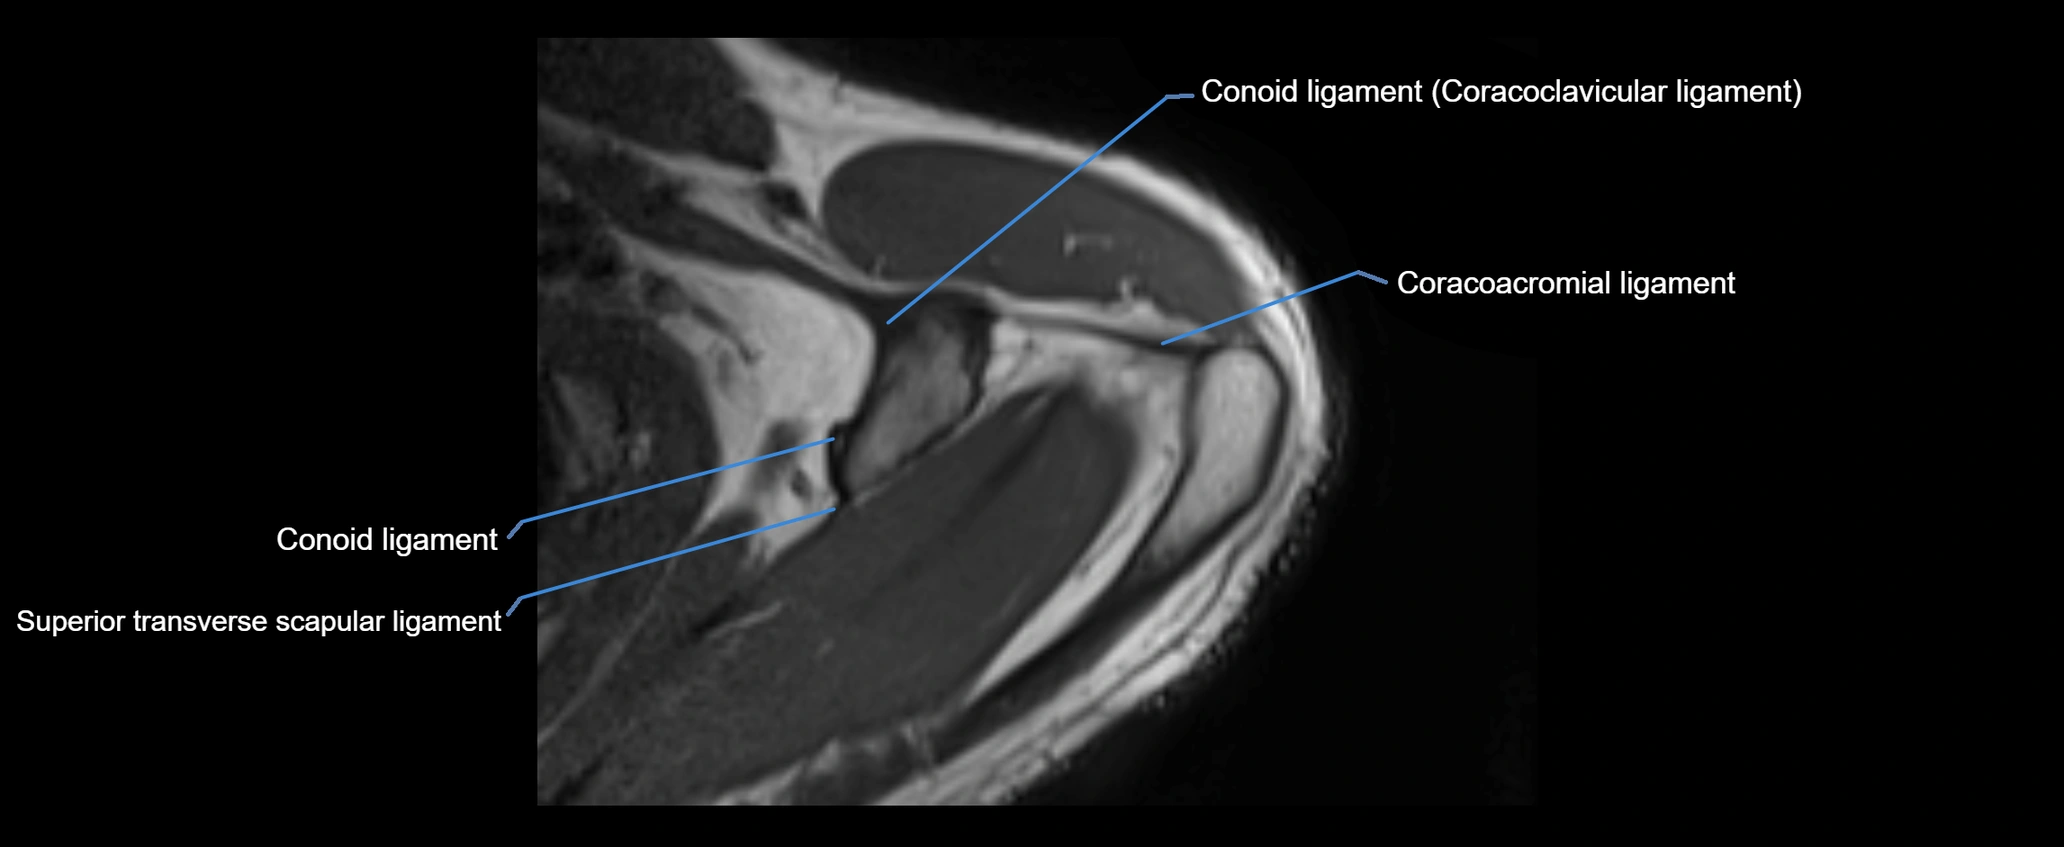

MRI images

image